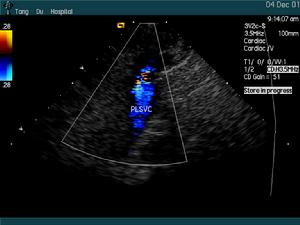

(4)超聲心動圖可見三尖瓣下移及下移程度。注意三尖瓣返流量、前瓣發育情況,有無房缺或卵圓孔未閉。

(3)切面超聲心動圖和都卜勒檢查顯示三尖瓣前瓣葉增大,活動幅度大。隔瓣葉和後瓣葉明顯下移,發育不良,活動度差。三尖瓣關閉延遲,瓣膜位置左移,室間隔動作反常。右心房及房化右心室共同顯示巨大的右心房腔,功能性右心室腔縱徑縮短。都卜勒檢查可顯示心房水平右向左分流和三尖瓣返流。